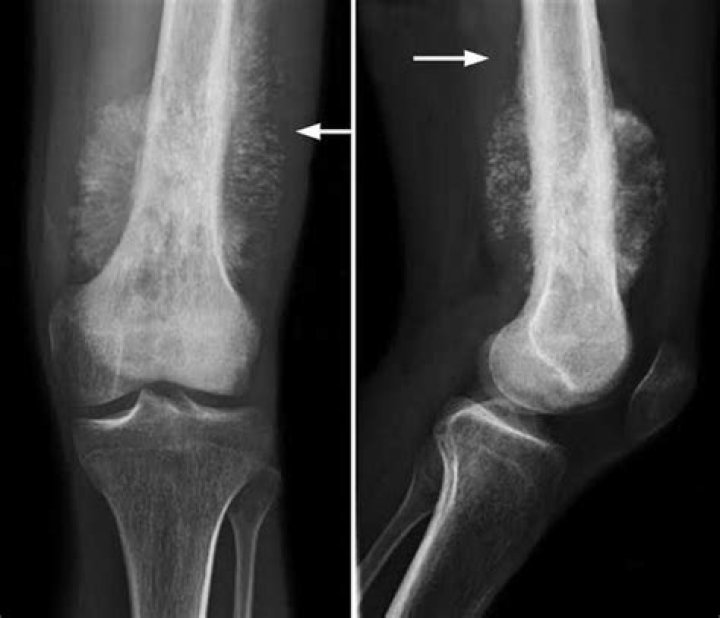

In children, teens, and young adults, osteosarcoma usually starts in areas where the bone is growing quickly, such as near the ends of the leg or arm bones: Most tumors develop in the bones around the knee, either in the lower part of the thigh bone (distal femur) or the upper part of the shinbone (proximal tibia).

Osteosarcoma commonly occurs in the long bones of the extremities near the metaphyseal growth plates. The most common sites are the femur (42%, with 75% of tumors in the distal femur), the tibia (19%, with 80% of tumors in the proximal tibia), and the humerus (10%, with 90% of tumors in the proximal humerus).